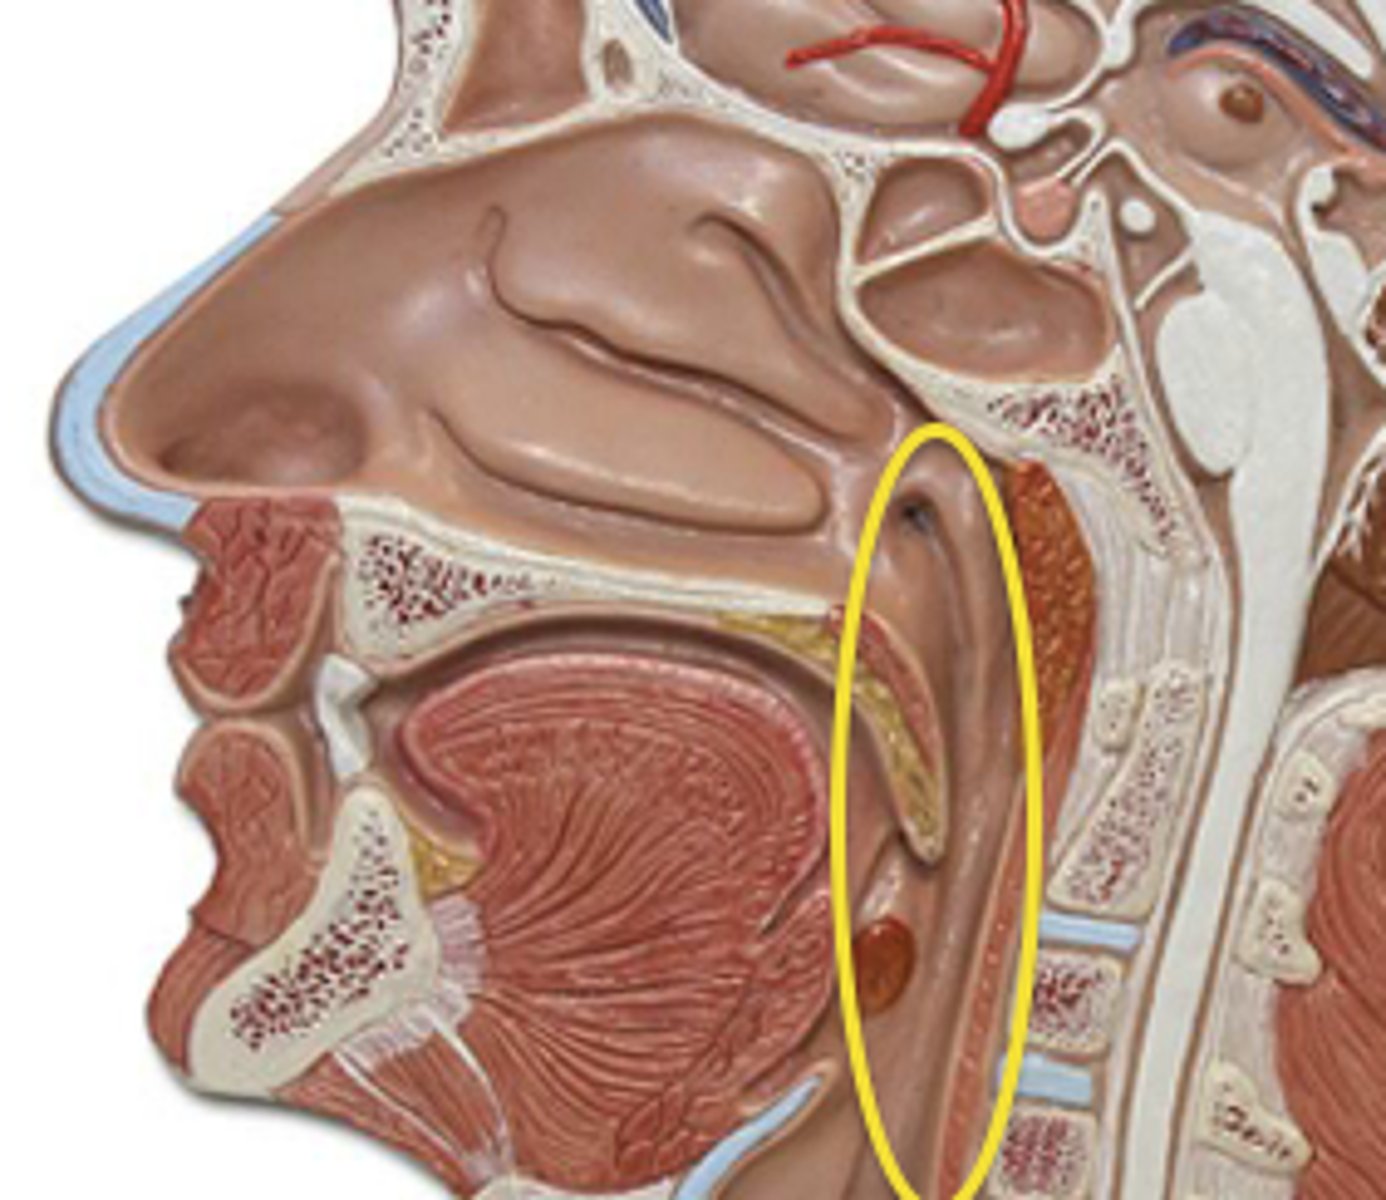

internal nares

knowt flashcard image

nasopharynx

laryngopharynx